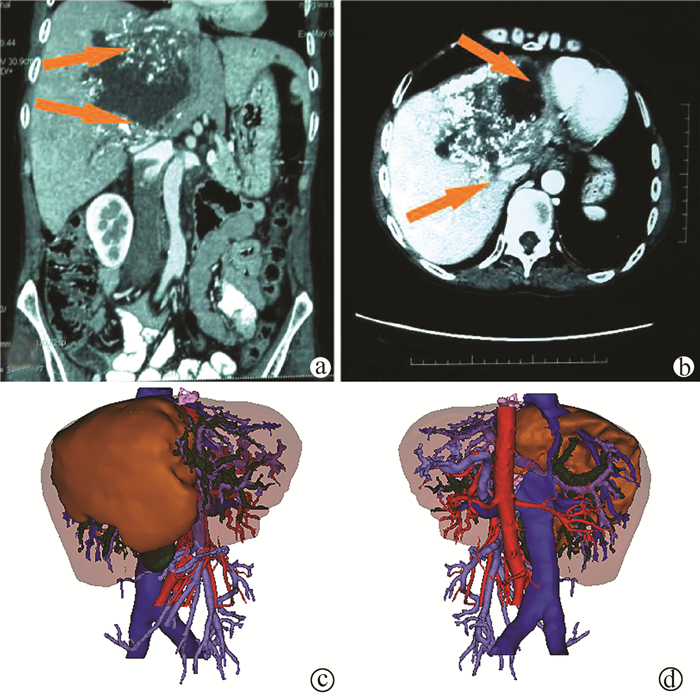

Application of liver three-dimensional visualized reconstruction technique in hepatectomy for children with complicated hepatoblastoma

Di ZHAO, Jindong YE, Huali LI, Kui JIN, Xiang LIU, Xiaoran LI, Liuxin DUAN, Jungui LIU, Wei LYU, Weihong DUAN, Quanda LIU

2021, 37(9): 2130-2135. DOI: 10.3969/j.issn.1001-5256.2021.09.025

Abstract(1328) HTML (405) PDF (3973KB)(66)

Abstract:

Objective  To investigate the application of liver three-dimensional (3D) visualized reconstruction technique in hepatectomy for children with complicated hepatoblastoma.  Methods  A retrospective analysis was performed for the clinical data of 30 children with hepatoblastoma who underwent hepatectomy for radical resection in PLA Rocket Force Characteristic Medical Center from January 2018 to October 2020, and according to whether liver 3D visualization with IQQA-Liver system was performed before surgery, the children were divided into 3D reconstruction group with 15 children and control group with 15 children. The two groups were compared in terms of perioperative parameters, short-term prognosis, and follow-up conditions. The independent samples t-test was used for comparison of normally distributed continuous data between two groups, and the Mann-Whitney U test was used for comparison of non-normally distributed continuous data between two groups; the Fisher's exact test was used for comparison of categorical data between two groups.  Results  Compared with the control group, the 3D reconstruction group had a significantly higher mean age (55.7±10.2 years vs 28.2±2.7 years, P < 0.05) and a significantly higher number of patients with POSTTEXT stage III/VI hepatoblastoma (12 vs 5, P < 0.05) or involvement of the hepatic vein or the inferior vena cava (11 vs 3, P < 0.05). All children completed the surgery successfully, and there were no significant differences between the two groups in blood loss, time of operation, number of times and duration of hepatic portal occlusion, and number of children receiving segmental hepatectomy or partial hepatectomy (all P > 0.05). The median follow-up after surgery was 9.5 months. In the 3D reconstruction group, 2 children experienced recurrence and were diagnosed at 10 and 12 months, respectively, after surgery, and they were treated with chemotherapy at the moment; in the control group, 4 children experienced recurrence, which was higher than that in the 3D reconstruction group (P=0.651), and among these 4 children, 2 had recurrence at 7 months after surgery, received liver transplantation, and survived up to now, and the other 2 children died shortly after recurrence.  Conclusion  3D visualized reconstruction technique helps to perform hepatectomy for children with complicated hepatoblastoma more safely and accurately, especially extended hepatectomy for patients with stage POST TEXT III/IV hepatoblastoma, thereby avoiding liver transplantation.